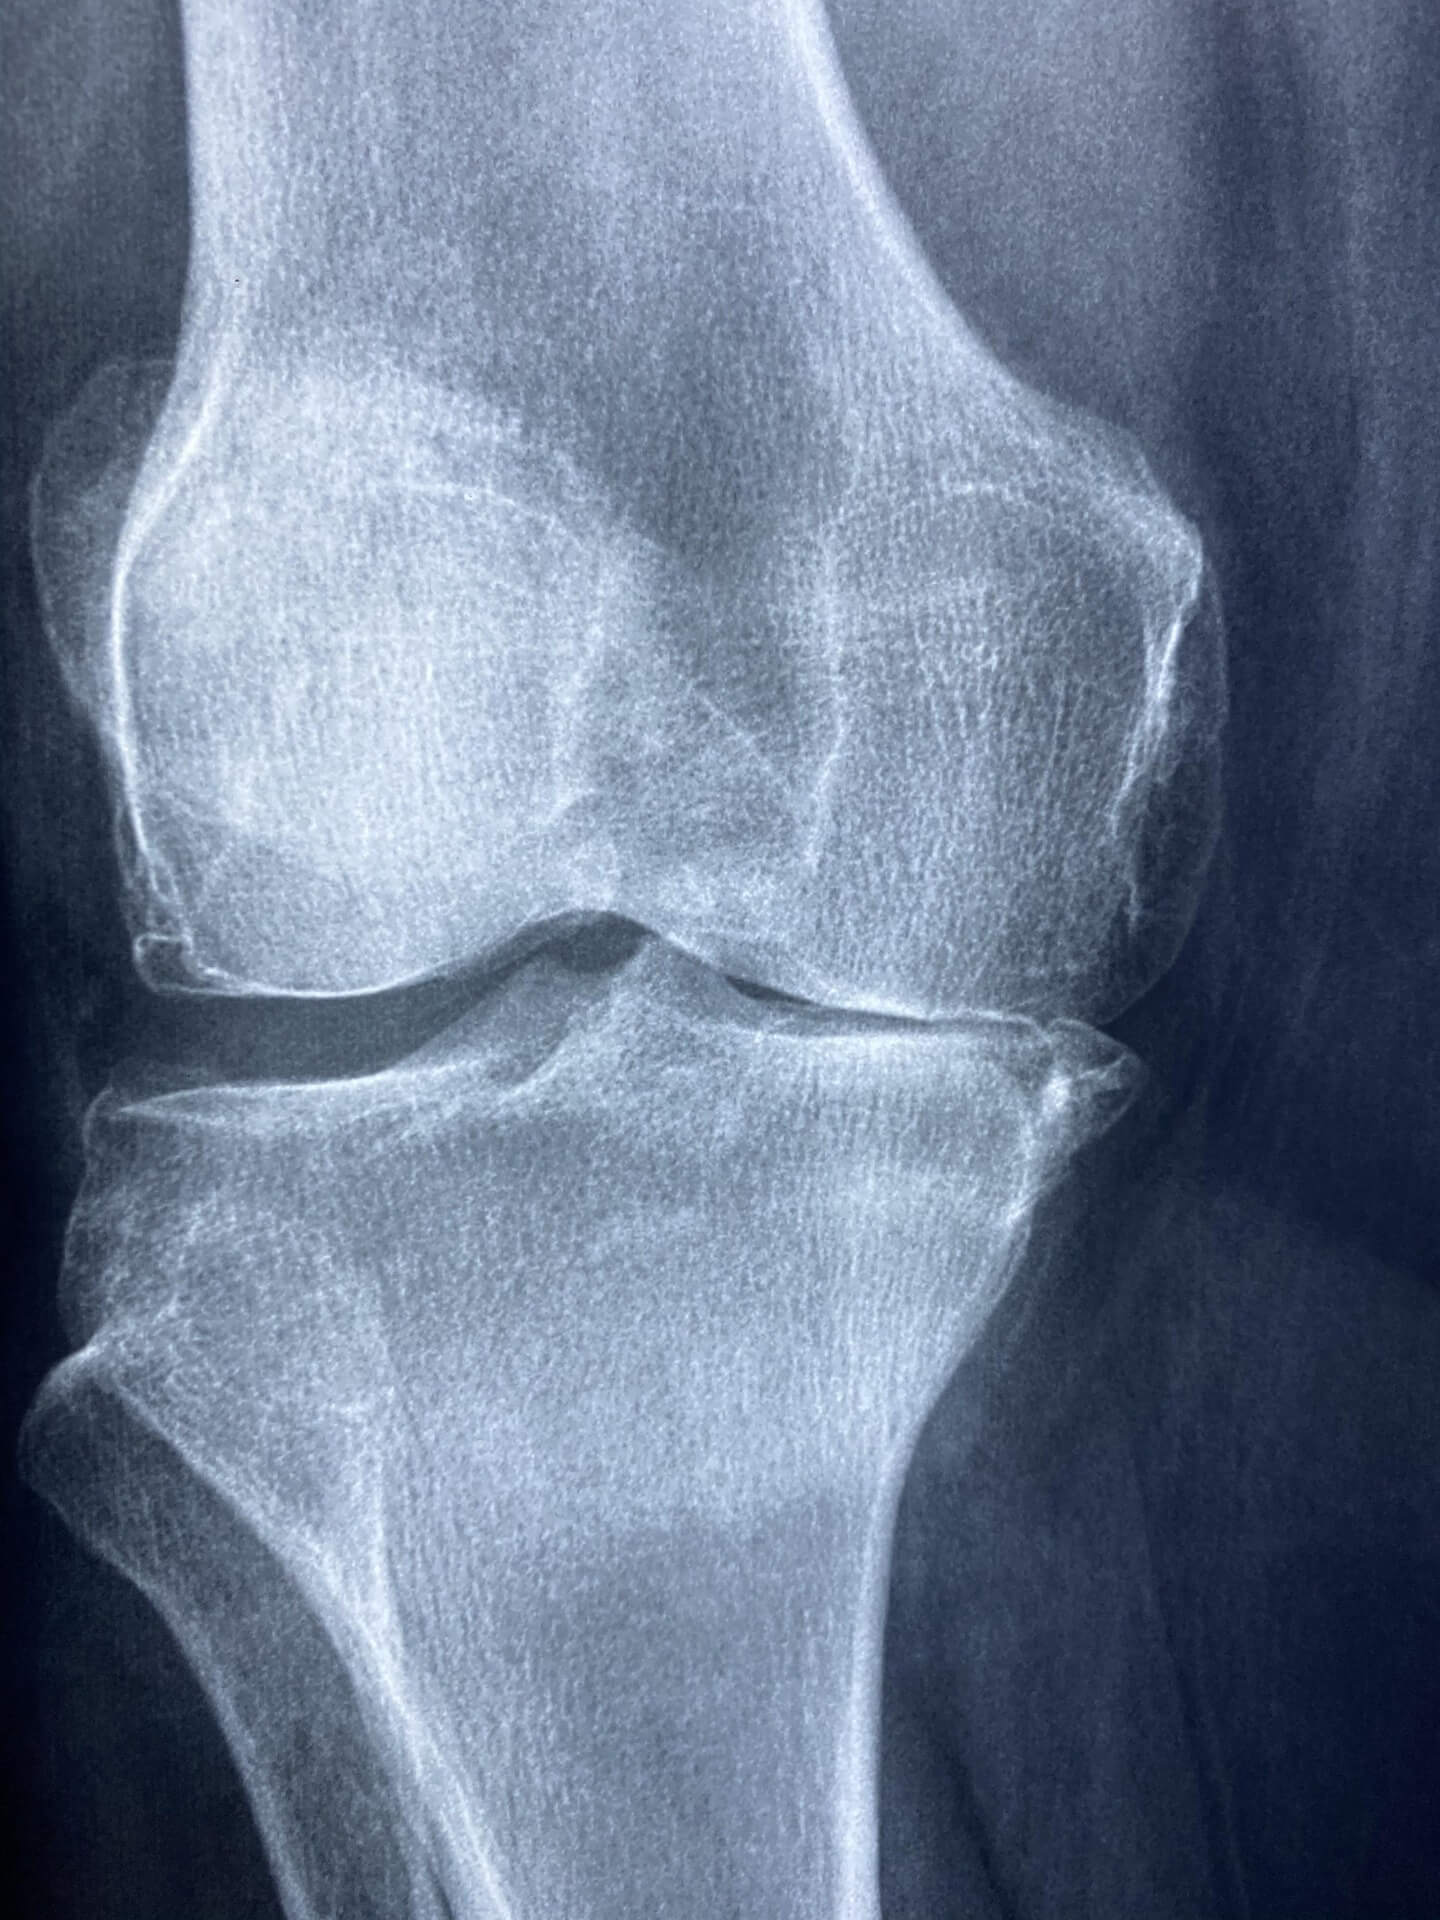

1-1. 관절염의 주요 원인과 증상

관절염은 유전, 노화, 비만, 잘못된 자세 등이 주요 원인입니다. 증상은 부기, 열감, 운동 시 통증 등으로 시작해 점점 관절 변형으로 이어질 수 있습니다.

최근 연구에 따르면, 꾸준한 관절염 완화 운동은 염증 물질 생성을 줄이고 연골을 보호하는 데 긍정적인 영향을 줍니다. 이는 약물치료만으로는 얻기 어려운 장기적인 개선 효과를 제공합니다.